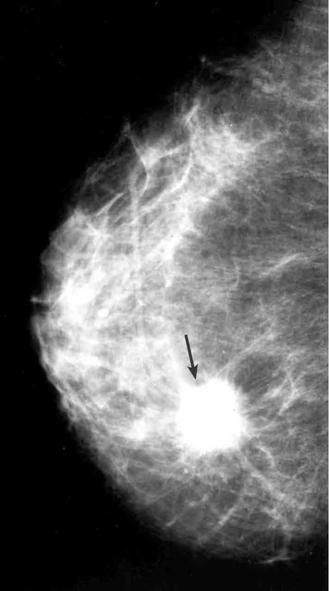

הבדיקה החשובה ביותר לגילוי מוקדם של שאתות השד היא הממוגרפיה. בבדיקה זו ניתן להדגים את רקמת השד, סמיכות הרקמה, הסתיידויות, עובי העור, צורתו וצל כלי הדם. צל בעל סמיכות יתר המכיל בתוכו מיקרוקלסיפיקציות במספר רב, בעל גבולות בלתי סדירים, כמו קרניים, עם זנב של רקמה סמיכה היוצאת ממנו, ריבוי והדגשה של כלי הדם או התעבות העור ושקיעת הפטמה, כולם מהווים סימנים מחשידים לקיום שאת ממארת בשד (תצלומים 22.12, 23.12). בהגדלה ניתן לראות את הסימנים לממאירות בצורה ברורה יותר (תצלום 24.12).

הסיבות אשר בעטיין נגע מסוים איננו ניתן למישוש הן: שאת קטנה, שאת המתבטאת רק בהסתיידויות זעירות ללא גוש (תצלום 25.12), שד גדול או מגורגר המקשה על הבדיקה הקלינית. הממוגרפיה, למרות יכולתה לגלות נגעים בלתי ניתנים למישוש, איננה בדיקה חד-משמעית וסגוליותה נמוכה. מחד גיסא, גוש סמיך בעל שוליים בלתי סדירים, עם הקרנת קוריות לסביבה מעיד בביטחון על תהליך ממאיר. מאידך גיסא, הסתיידויות גסות, הסתיידויות כיסתיות או הסתיידויות פסיות סדירות וכן נגעים בעלי סמיכות דומה לזו של שומן, מצביעים על תהליך שפיר.

מרבית השאתות הממאירות המתגלות באמצעות ה-Screening mammography, הן מדרגה I, לעומת הבדיקה הקלינית, המאבחנת לרוב שאתות בשלבים מתקדמים יותר. הישג זה ראוי לציון, מאחר שניתוח בשלב ראשוני, משפר את תוחלת החיים. מקובל כיום, שממצאים ממוגרפיים החשודים לשאת ממאירה, מהווים הוריה לביופסיה. ואמנם כ-30%-20% מהם מוכחים כממאירים בבדיקה הפתולוגית.